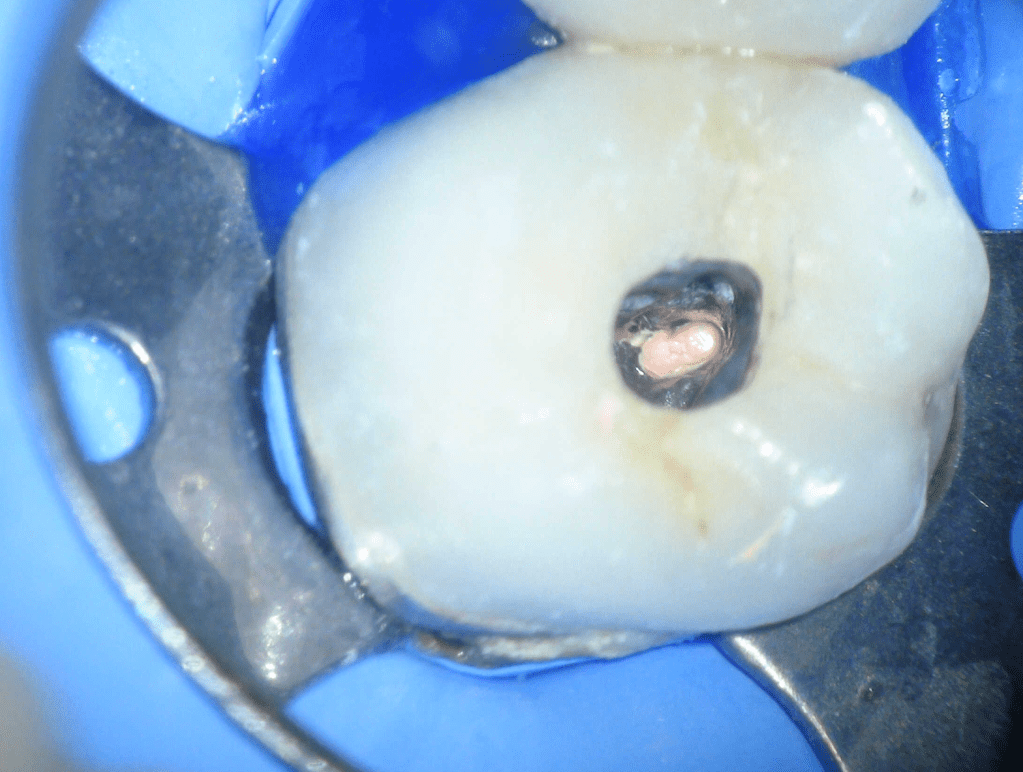

Pulpotomía biodentine + reco preendio